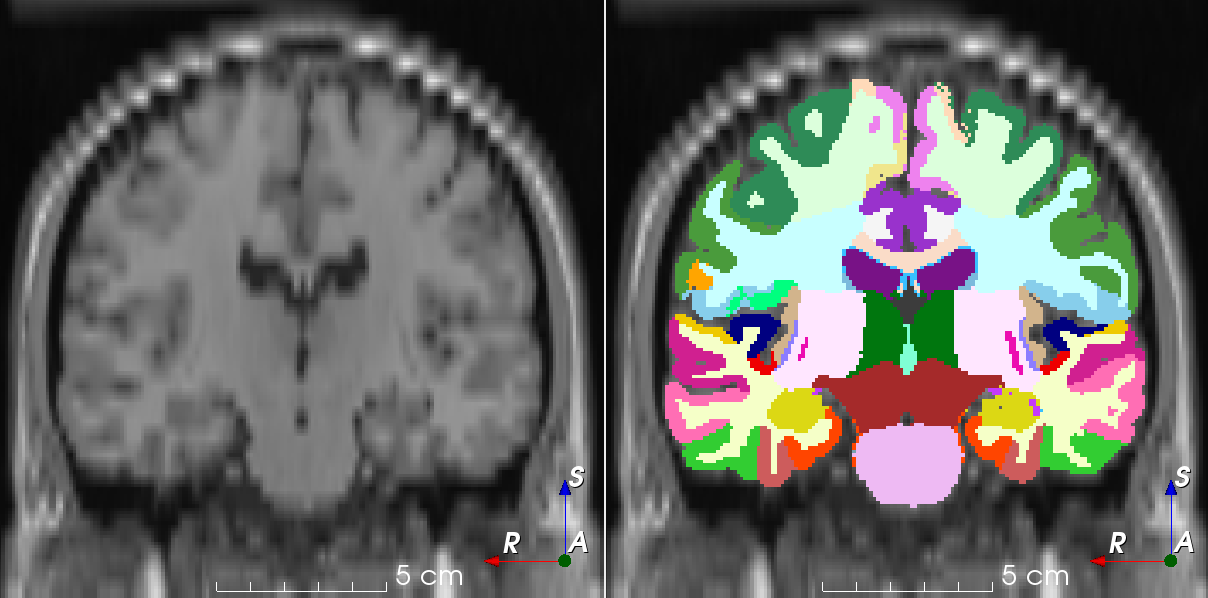

Downsample an image along an axis and upsample to initial space.

This transform simulates an image that has been acquired using anisotropic spacing and resampled back to its original spacing.

Similar to the work by Billot et al.: Partial Volume Segmentation of Brain MRI Scans of any Resolution and Contrast .